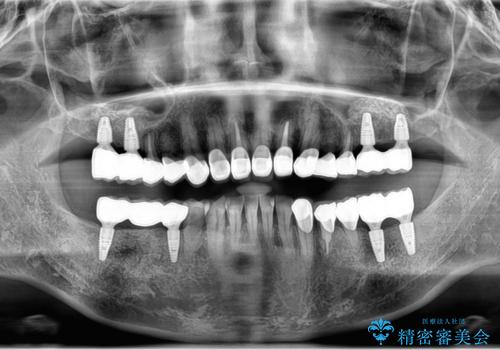

- 大人になっても残存していた乳歯がグラグラし、痛くて噛めない 抜いて欲しいとの希望で来院されました。

歯根が吸収し残すことのできない乳歯を抜去後、隣の歯を削らずに済むインプラント治療で咬合機能の回復を計画します。

- 44万円(インプラント・チタンカスタムアバットメント・ジルコニアクラウン・仮歯)費用は治療当時の料金となります

乳歯の抜去後、インプラントを用いてしっかりと咬合機能を回復することができました。